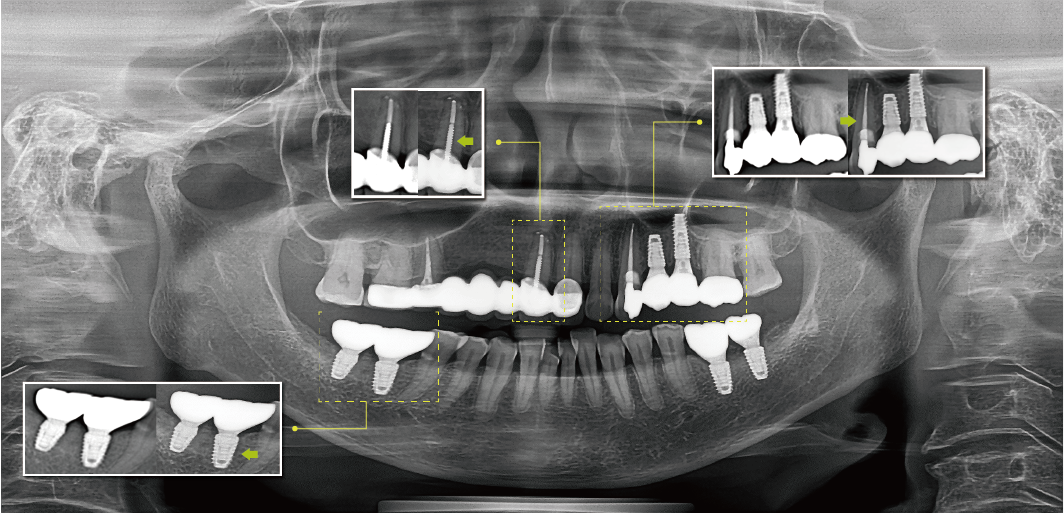

清晰的全景影像

通過多層技術(shù),可以拍攝多張圖像,每張圖像被進(jìn)一步分割。系統(tǒng)會(huì)自動(dòng)選擇最佳焦點(diǎn)將其整合成一個(gè)優(yōu)化的全景圖像。

前牙部畸變縮小,即使不單獨(dú)拍攝小牙片,也能準(zhǔn)確診斷。清晰度可準(zhǔn)確識(shí)別種植體螺紋和內(nèi)部,確保連接程度和斷裂程度。